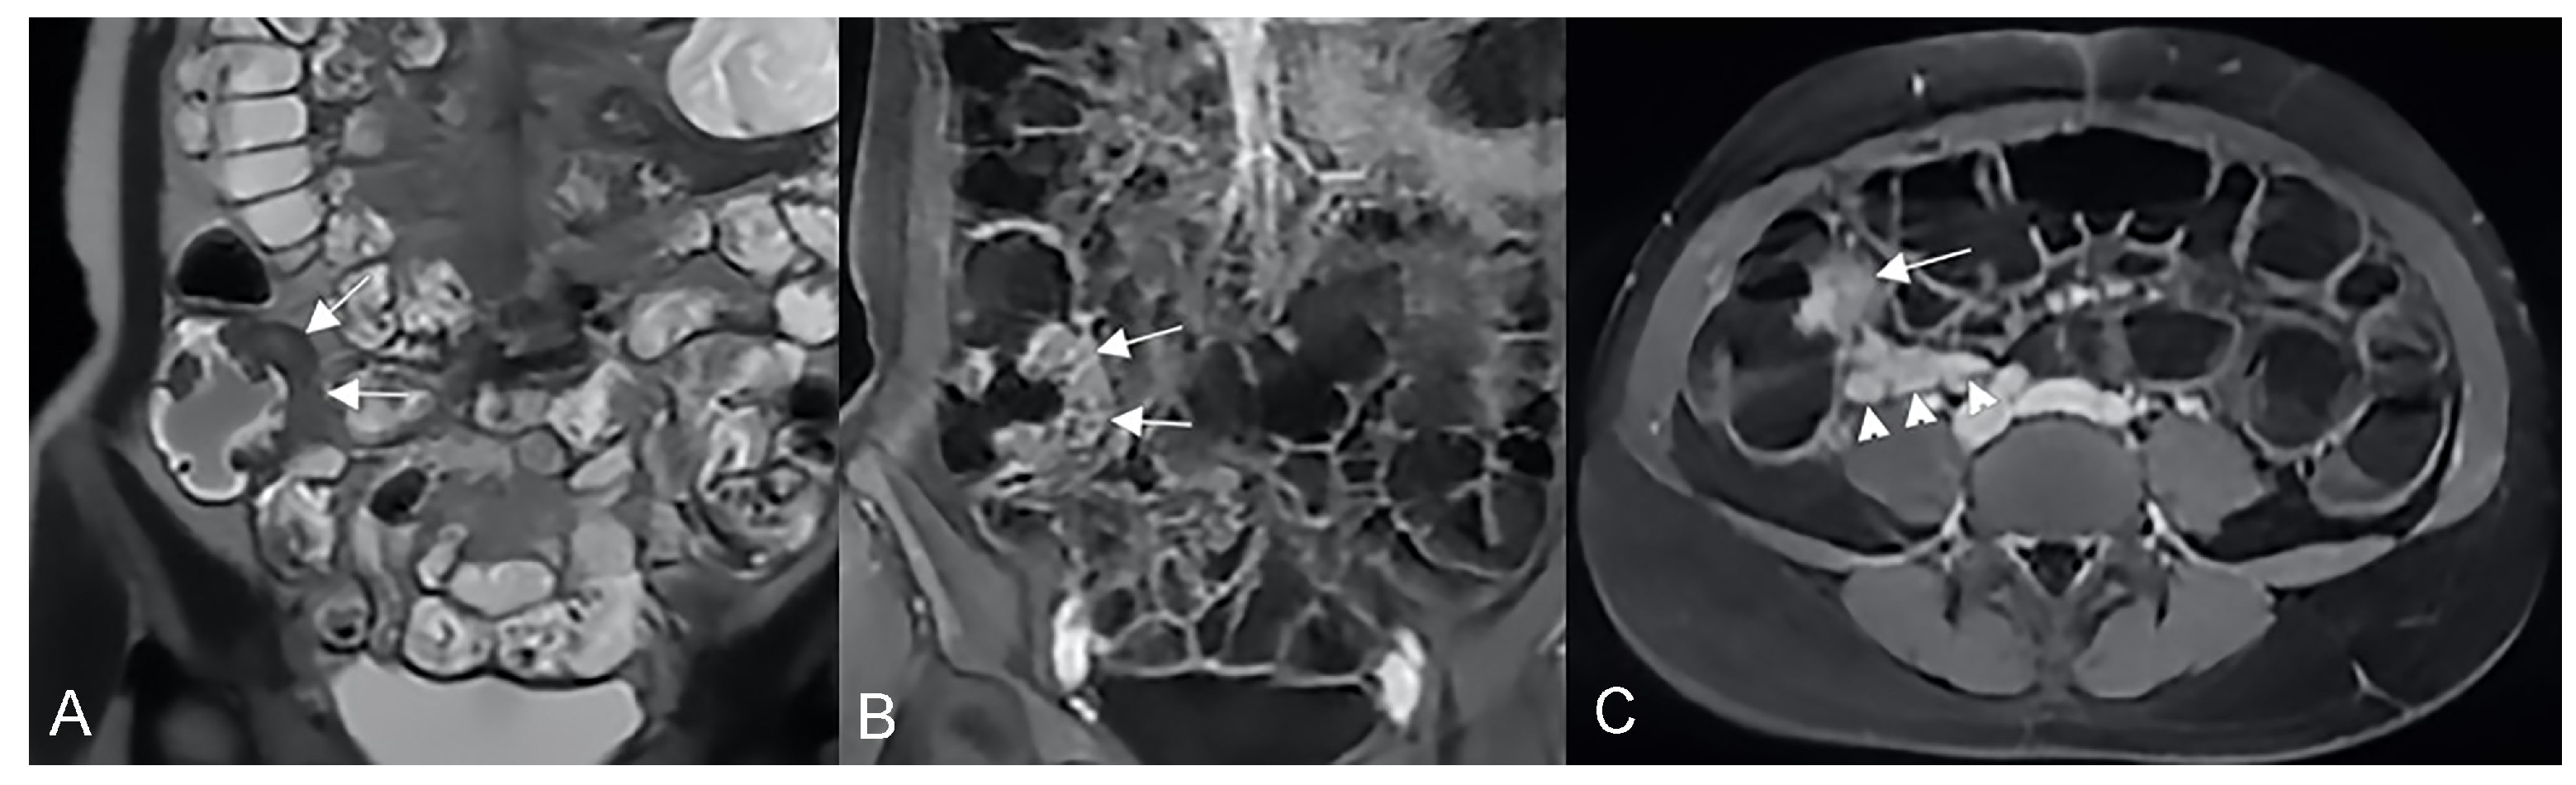

Figure 12.

Inflammatory conglomerate represents a climbing mesenteric fat involvement in the context of penetrating disease and mesenteric inflammation. The components of the fistulas within the mass can be difficult to detect because it often coexists with phenomena of retraction that are expressed on the intestinal loops nearby or on the ureters. Small inflammatory conglomerate in the context of the mesentery adherent to a segment of the pathological small intestine, with active disease (yellow arrowheads in (A,C): coronal (A) and axial (C) contrast-enhanced fat-suppressed T1-weighted image and in (B,E) (coronal fast imaging employing steady-state acquisition; FIESTA image) and (D) (coronal T2-weighted MRE image)).

Figure 13.

Two different patients with, respectively, an inflammatory conglomerate (Patient 1) of medium size (yellow arrowheads in (A–C)) and of large size (green arrowheads in (D–F)) (Patient 2). Coronal (A,B) and axial (C) fast imaging employing steady-state acquisition (FIESTA) image. Coronal FIESTA image (D) and coronal without (E) and with (F) contrast-enhanced fat-suppressed T1-weighted image. Notably intense contrast enhancement in (F) image underlines the significant state of inflammation of the disease in the active and complicated phase.